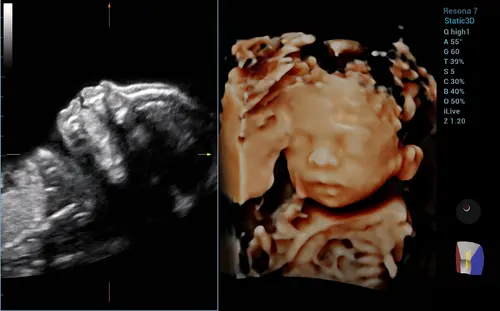

Dit was de echo van ons ventje... al met 22 weken gedaan toen ik in Nederland was. Vandaag 27 weken alweer.